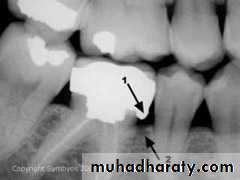

In addition, open contacts have been associated with increased loss of alveolar bone, most probably through food impaction.